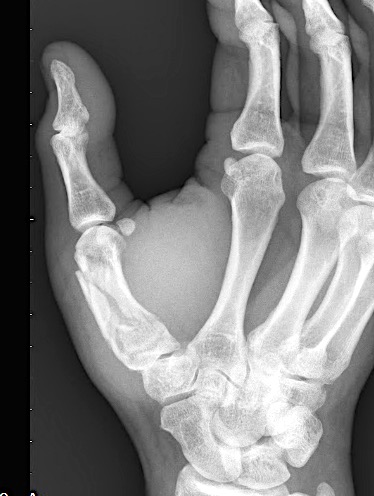

A 64-year-old male suffered a multi-fragmentary fracture of his right thumb metacarpal (Fig 1). An adapted 12-hole strut plate from the variable angle locking hand system was the implant of choice for fixation (Figs 2 - 4).

The strut plate provided good stability in a comminuted extraaricular fracture pattern and enables immediate mobilization. Bone callus formation was not witnessed during the healing process.